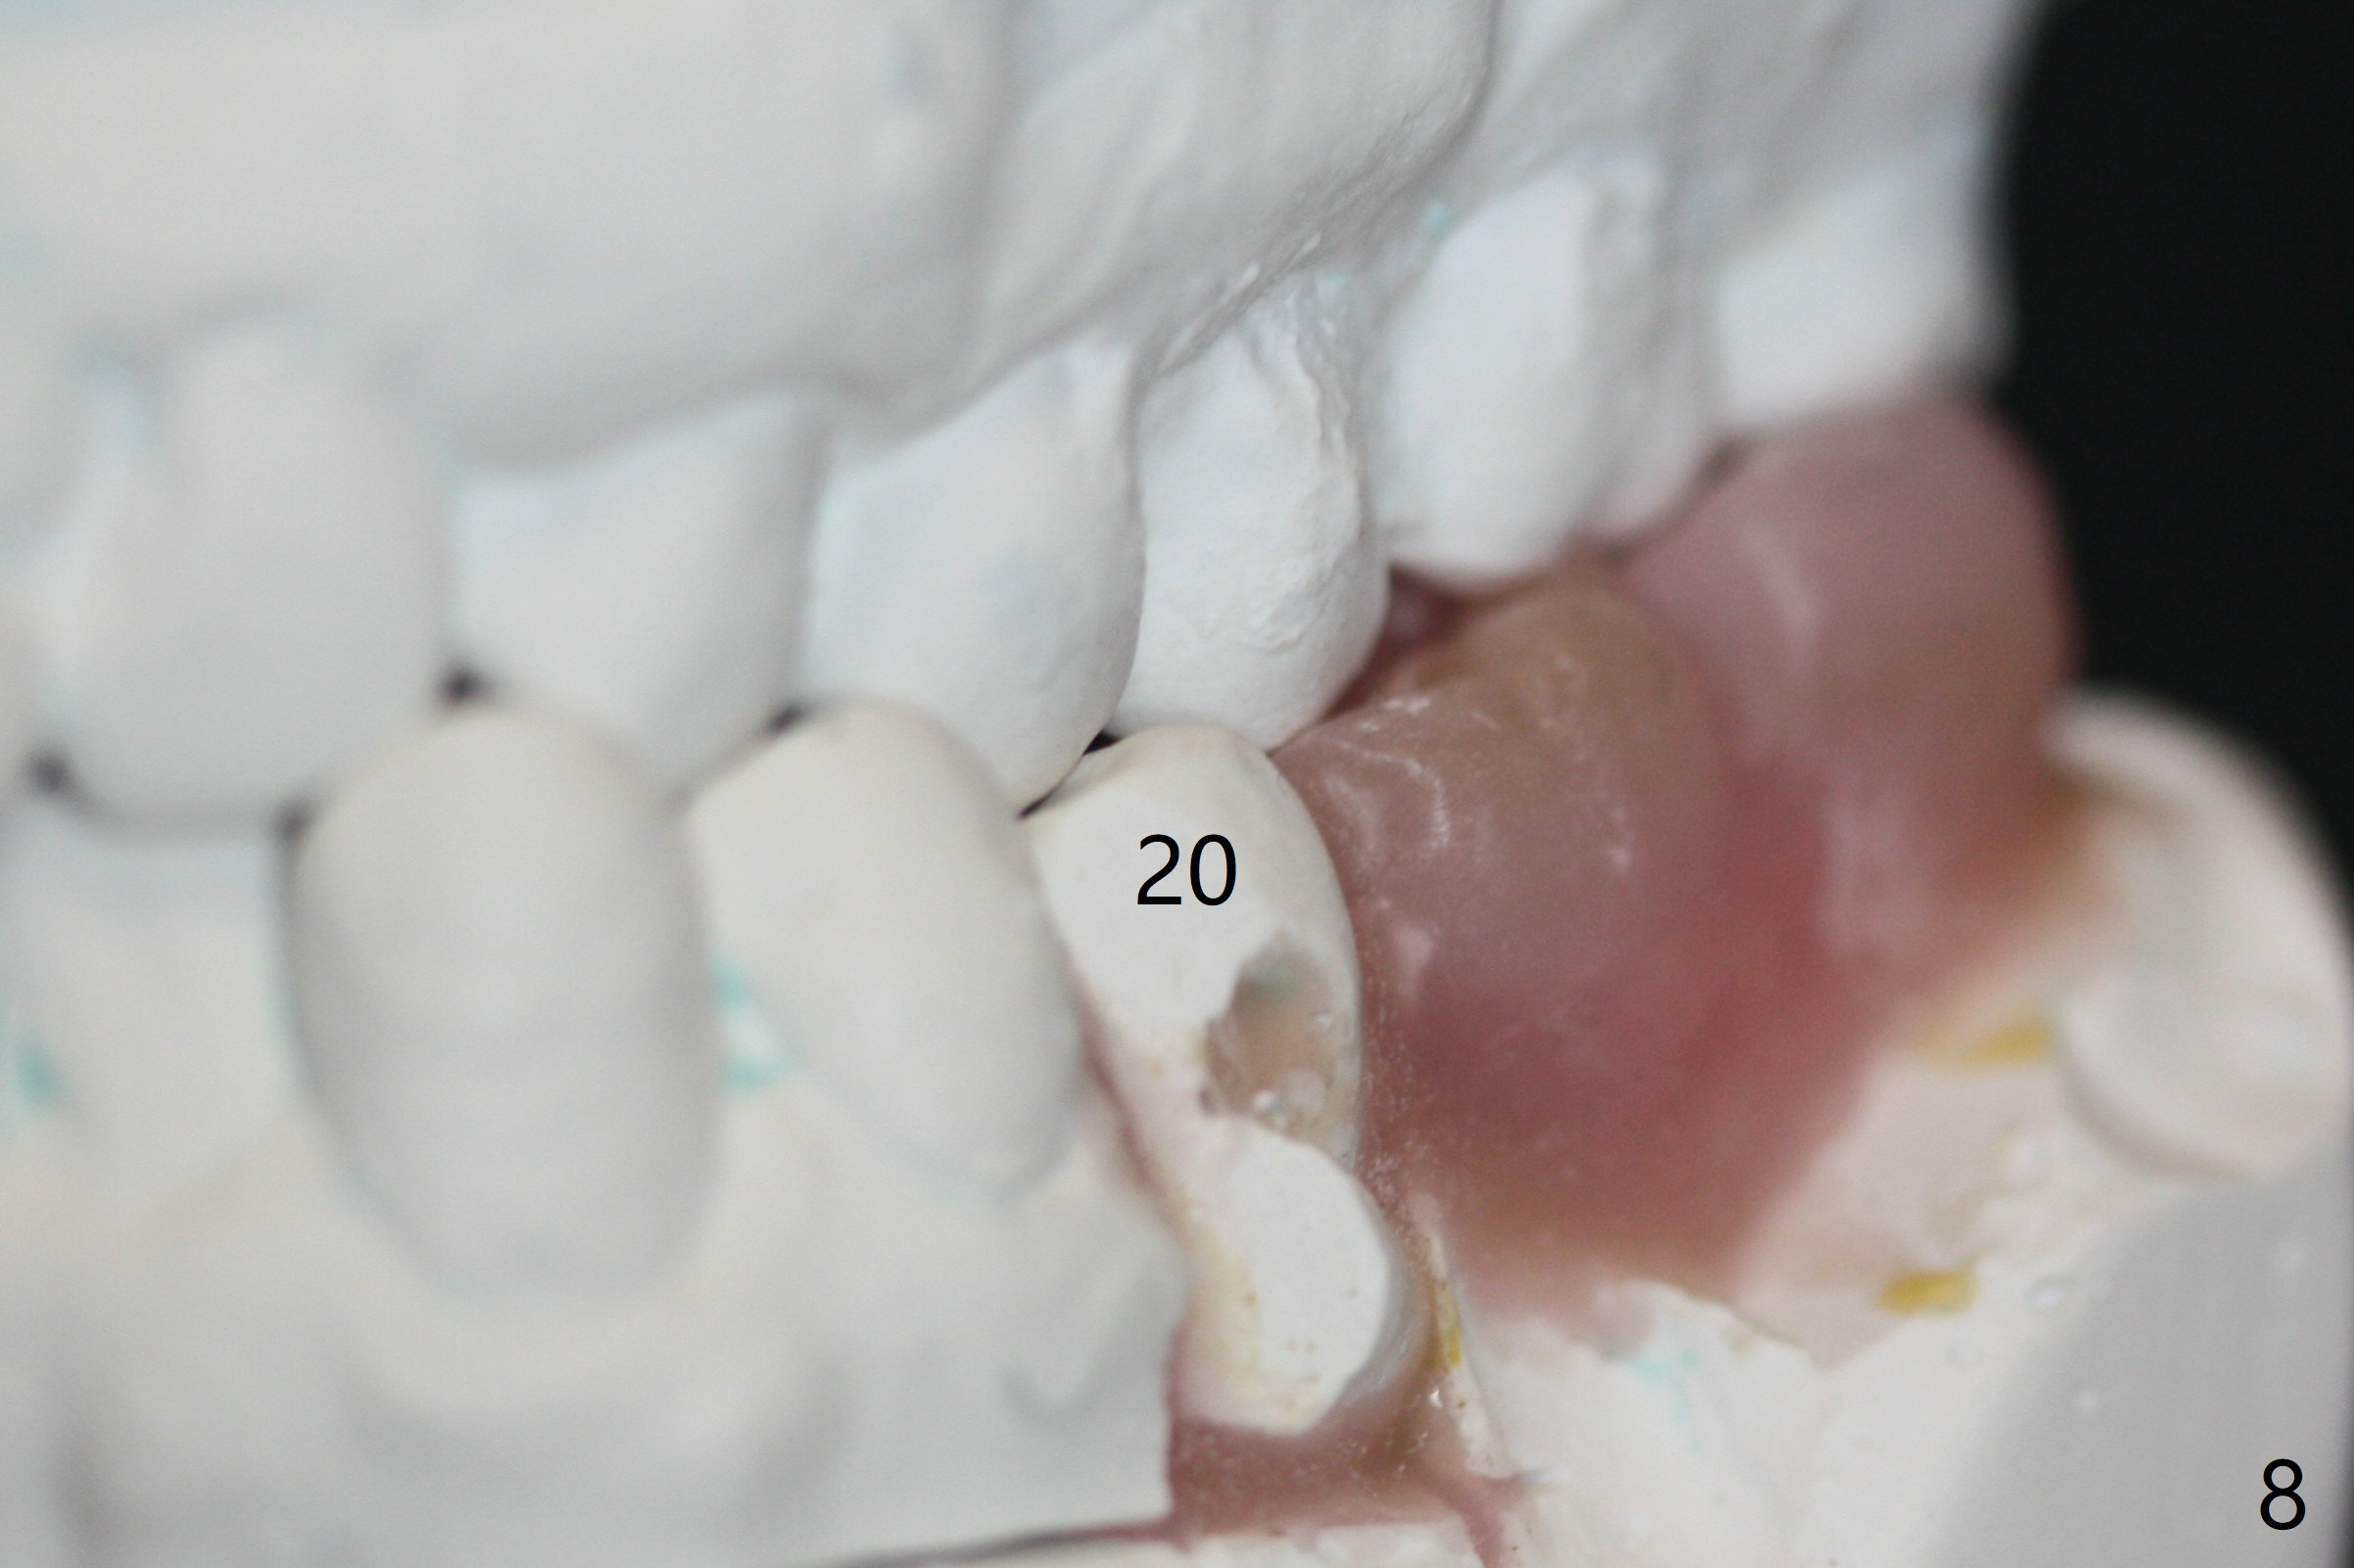

A 43-year-old man has poor dentition on the left: 1st molar missing, 2nd molar mesial inclination (Fig.1) and 2nd bicuspid lingual tilt (Fig.2). The latter is nonfunctional (Fig.3 (linguoposterior view). Two molar implants will be placed in a position so that their crowns will be in cross bite (Fig.4,5), the same occlusal scheme as the teeth #21 and 22. When these implants osteointegrate, the provisional crowns (Fig.6 P) will be supraocclusal so that there is clearance (*) for #20 to upright orthodontically (Fig.7-9). Moreover, these implants will be used anchorage as well as #21 and 22. Panoramic X-ray (Fig.1) and CBCT (Fig.10-12) show limited bone height at the sites of #18 and 19. It appears that 5x8 and 5.9x6 mm implants are appropriate with ridge reduction at #19.